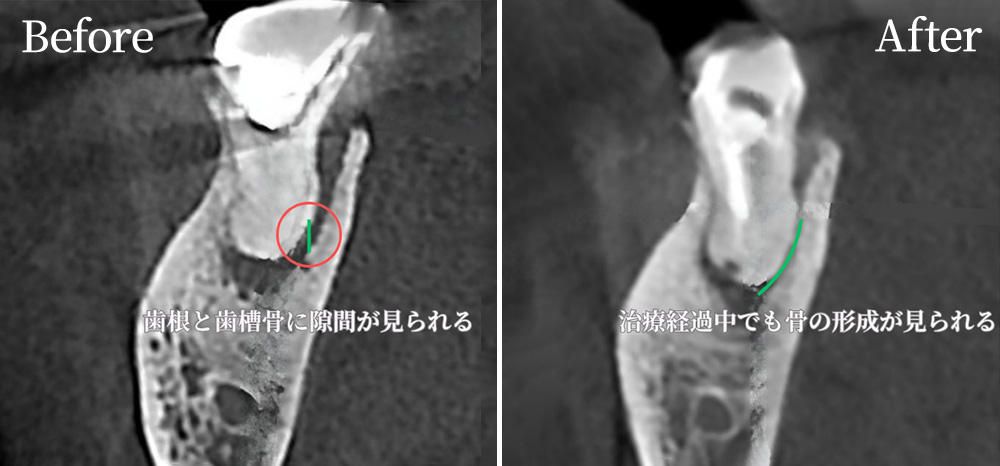

根管治療の症例

CT画像により、奥歯の根の一部に根管治療の痕跡が見られます。

また、根の周囲に透過像(黒く抜けた部分)があり、これは過去の感染や慢性的な炎症が疑われます。

肉眼や通常のレントゲンでは確認が難しい細かい構造や、根管の分岐・湾曲・追加根管の有無がCTによって明瞭に見えています。

他院では抜くことを勧められる症例ですが、当院ではできる限り自然の歯を残すことを第一に考え、マイクロスコープ(歯科用顕微鏡)や歯科用CTを利用しながら、精密な診断と治療を行っています。